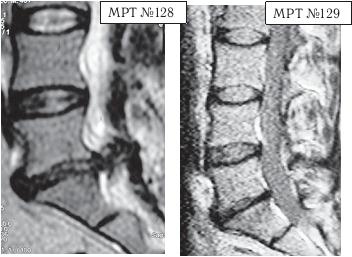

![]() На МРТ № 124 состояние поясничного отдела позвоночника (до применения метода вертеброревитологии): в сегменте LIV-LV наблюдается выраженный дегенеративный процесс в межпозвонковом диске с разрушением пульпозного ядра, снижением его высоты; в сегменте LV-SI наблюдается секвестрированная грыжа межпозвонкового диска с разрывом задней продольной связки, абсолютный стеноз спинномозгового канала. На МРТ № 125 того же пациента отмечается состояние поясничного отдела позвоночника после двух курсов лечения методом вертеброревитологии: в сегменте LV-SI наблюдается отсутствие грыжи межпозвонкового диска, спондилёз, небольшой участок гипертрофии задней продольной связки (в месте разрыва). Но самое примечательное то, что особо интересует вышеуказанных профессиональных специалистов, — в межпозвонковых дисках отмечен активный процесс репаративной регенерации. А в межпозвонковом диске в сегменте LIV-LV он практически достиг полной реституции! ![]() сегмент LIV-LV (до лечения) сегмент LIV-LV (после лечения) Примечание: как правило, на качественных снимках МРТ, очень чётко просматривается состояние диска, благодаря цветовой гамме. Тёмные участки межпозвонкового диска соответствуют участкам расположения некротизированных тканей (мёртвых клеток). Светлые участки межпозвонкового диска соответствуют участкам расположения функциональных тканей (живых клеток). Другой интересный случай — устранение секвестрированной грыжи с соответствующей активацией процесса восстановления межпозвонковых дисков. К сожалению, в последнее время остеохондроз всё больше охватывает молодое поколение. Повальная гиподинамия — нарушение функций опорно-двигательного аппарата, кровообращения, дыхания, пищеварения и так далее вследствие ограничения двигательной активности — распространённое явление среди молодёжи. Приведённый ниже случай является довольно типичным в моей врачебной практике.

На МРТ № 128 наблюдается состояние поясничного отдела позвоночника после операции: рецидив грыжи межпозвонкового диска в сегменте LV-Sr с отрывом секвестра и его миграции в краниально-дорсальном направлении, разрыв задней продольной связки. На МРТ № 129 наблюдается состояние поясничного отдела позвоночника после лечения методом вертеброревитологии: отсутствие грыжи межпозвонкового диска в сегменте L — S. В межпозвонковых дисках в сегментах LIV-LV, L — SI наблюдается процесс репаративной регенерации. ![]() На МРТ № 130 наблюдается состояние поясничного отдела позвоночника после двух хирургических операций: рецидив грыжи межпозвонкового диска в сегменте LV-SI. На МРТ № 131 наблюдается состояние поясничного отдела позвоночника после лечения методом вертеброревитологии. Рецидив грыжи межпозвонкового диска после двух хирургических операций — и это у молодого человека в возрасте 16 лет! Чрезмерное увлечение компьютером, малоподвижный образ жизни основательно подорвали его здоровье. Всё это привело к тому, что в течение года, начиная с пятнадцатилетнего возраста, он практически не выходил из больниц. После первой хирургической операции на позвоночнике, менее чем через месяц, боли возобновились. Спустя два месяца его вновь прооперировали по поводу рецидива — грыжи межпозвонкового диска. После второй хирургической операции боли наблюдались практически два месяца подряд, потом затихли, но полностью так и не прошли. Через пять месяцев появилась слабость в обеих ногах. Сделали снимки МРТ, диагностировали рецидив грыжи межпозвонкового диска, естественно рекомендовали сделать очередную третью хирургическую операцию. В промежутках между операциями молодой пациент несколько раз находился на стационарном лечении в неврологическом отделении городской больницы. Именно там, после того как у парня была диагностирована очередная грыжа, лечащий врач посоветовал не спешить с третьей операцией и порекомендовал ему обратиться ко мне в клинику. Конечно, этот случай был далеко не простым и пришлось основательно потрудиться как мне, так и самому пациенту над восстановлением его здоровья. Но зато результат порадовал всех тех, кто непосредственно участвовал в этом процессе, и кто косвенно ему способствовал. Можно сказать, ещё одна судьба была изменена и молодой человек спасён от инвалидной коляски. МРТ № 132МРТ № 133 ![]() На МРТ № 132 и МРТ № 133 — увеличенные фрагменты МРТ № 130 межпозвонковых дисков в сегментах LIV-LV и LV—SI до лечения методом вертеброревитологии. Структура межпозвонковых дисков неоднородна. ![]() На МРТ № 134 и МРТ № 135 — увеличенные фрагменты МРТ № 131 межпозвонковых дисков в сегментах LIV-LV и LV—SI, после лечения методом вертеброревитологии. Наблюдается весьма интересное явление — репаративная регенерация. Обратите внимание, насколько уменьшилось количество некрозной (мёртвой) ткани и увеличилось функциональной (живой) ткани. Примечательно, что хондроциты при регенерации в данной фазе формируют вертикальные и наклонные «колонны» согласно вектору нагрузки на межпозвонковый диск в районе фиброзного кольца. В центре межпозвонкового диска наблюдается не менее интересное явление — начало регенерации пульпозного ядра! Следующий случай можно назвать абсолютно беспрецедентным в истории науки вертебрологии и новым этапом в развитии вертеброревитологии. С помощью метода вертеброревитологии удалось практически полностью восстановить (по сути заново вырастить) отсутствующий межпозвонковый диск! И это без всяких химических препаратов, а исключительно благодаря естественному восстановлению биомеханики позвоночника — выстраиванию определённой биомеханической конструкции. При построении последней были достигнуты оптимальные условия для активизации резервных возможностей организма, что, в свою очередь, способствовало запуску репаративной регенерации вплоть до реституции диска, который в своё время был практически полностью удалён. Это удивительное явление, сравнимое разве что с реанимацией. Впрочем, всё по порядку. |